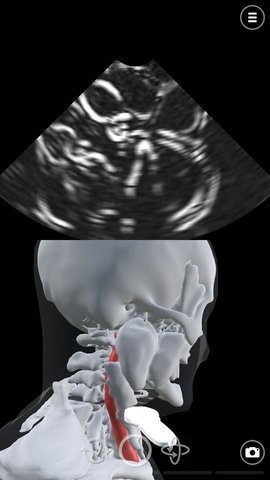

超声模拟器是一款非常有趣的游戏,它可以让玩家了解超声波的工作原理,并在实践中应用。这款游戏可以用于急诊(ER)超声、外科(术前)超声、骨科超声扫描、类风湿性超声、血管超声,眼科超声和麻醉超声(麻醉学)等方面的应用。玩家可以在游戏中尝试各种有趣的操作,一起玩耍。

1、超声模拟器游戏中模拟了基本超声波或超声波探头运动,使用先进的计算机图形来模拟声波,超声扫描相关解剖,超声心动图或超声心动图,并模拟简单的超声波检查。

3、这款游戏的玩法非常有趣,玩家可以看到人在收到超声波影响下的画面,极为流畅的动画。